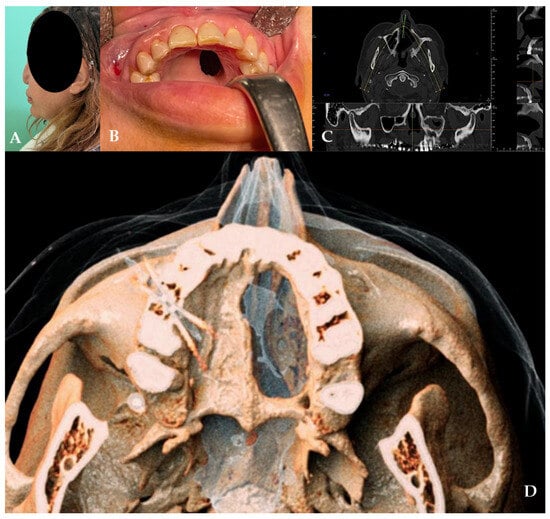

A 49-year-old female patient came to our attention in 2021, presenting a palatal/oro-nasal fistula measuring 2 cm in diameter along the major axis and with atrophic and burned soft tissue surrounding the lesion (Ia according to the Okay et al. classification [14]).

The patient was treated with an obturator to permit correct speech and feeding. At the clinical and radiographic examination, there was also wide, bony, and cartilaginous septal destruction with communication of the nasal cavity and collapse of the nasal pyramid. Speech disturbances, rhinolalia, and eating difficulties were observed (Figure 1).

Figure 1. (A,B) Clinical presentation of the oro-nasal communication. In inset (A), it is possible to appreciate the collapse of the nasal pyramid. (C,D) Radiographic and 3D reconstruction using InVivo6® and Anatomage Table EDU vers.8® (Santa Clara, CA, USA) software. DICOM files were imported in InVivo6® (Santa Clara, CA, USA) software to obtain the axial, cross, and panorex sections. Afterwards, the DICOM files were imported Anatomage Table EDU vers.8® (Santa Clara, CA, USA) to obtain the 3D rendering.